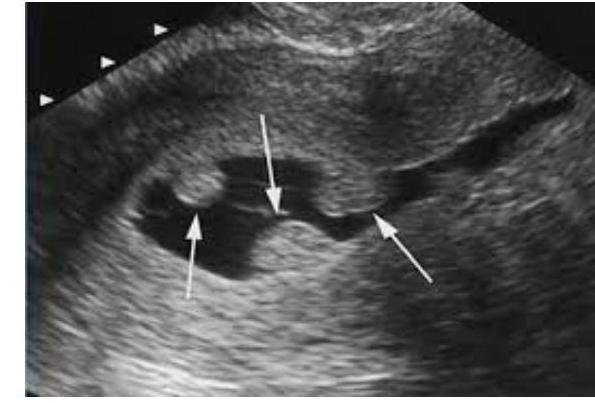

# SANGRADO UTERINO ANORMAL ## DEFINICIÓN El Sangrado Uterino Anormal es la variación del ciclo menstrual normal, e incluye cambios en la regularidad, frecuencia del ciclo, y duración del flujo o en la cantidad de sangrado menstrual asociadas a disturbios médicos que sólo pueden ser identificados por una historia clínica orientada a búsqueda de etiología complementando con métodos de laboratorio, gabinete y determinaciones hormonales como por ejemplo coagulopatías, disfunciones ovulatorias o desordenes primarios endometriales. ## TERMINOLOGÍA | DURACIÓN NORMAL | Pérdida de sangrado menstrual de 3 - 7 días. | | :--: | :--: | | CICLO REGULAR | Se presenta con una variación normal de ciclo a ciclo de +2 hasta 20 días. | | CANTIDAD NORMAL | Sangrado menstrual entre 30 - 80 ml por ciclo (promedio 60 ml ) 1 toalla sanitaria nocturna =20 ml | | FRECUENCIA MENSTRUAL NORMAL | Presencia de intervalos de sangrado de 25 -35 días. | Polimenorrea: es un patrón de sangrado periódico y regular, pero con una frecuencia menor a 21 días. Hipomenorrea: son sangrados uterinos regulares, de duración normal, pero en cantidad reducida. Metrorragia: es un sangrado uterino que aparece fuera del periodo menstrual de cantidad es variable. Menorragia: es la pérdida ginecológica excesiva, con características de hemorragia importante, de duración prolongada y que aparece a intervalos regulares Hipermenorrea: son sangrados uterinos regulares, de duración normal, pero en cantidad excesiva (mayor de 80ml ). Oligomenorrea: es un patrón de sangrado periódico pero con una frecuencia mayor a 35 días. ## EPIDEMIOLOGÍA - El SUA es una condición frecuente, el cual tiene un impacto social y económico significativo. - Considerada como la segunda causa de consulta ginecológica, después de las infecciones cervicovaginal; por su origen puede ser de tipo anatómica o disfuncional. \Rightarrow 9 al 14 % de las mujeres en edad reproductiva han tenido ciclos menstruales mayores a 80 mililitros por ciclo menstrual - El tratamiento médico debe ser indicado entodos los casos, y si no hay respuesta al mismo, se decidira tratamiento quirúrgico según el caso. - La causa más frecuente de HEMORRAGIA POST-MENOPAÚSICA es ATROFIA ENDOMETRIAL, sin embargo, siempre se debe descartar que sea por Cáncer de Endometrio. # ETIOLOGÍA La clasificación actual de la hemorragia uterina anormal propuesta por a FIGO en 2011 conocida como PALMCOEIN , estratifica en 9 categorías de acuerdo al acrónimo. ## SANGRADO ANORMAL Pólipos Adenomiosis Leiomioma Malignidad/Hiperplasia  SANGRADO DISFUNCONAL | Coagulopatía | | :-- | | Ovulatory Disfunción | | Endometrial | | latrogénica | | No Clasificada |  ## DIAGNÓSTICO ## GOLD STANDARD: BIOPSIA DE ENDOMETRIO - Descarta patología endometrial por histopatología ## 1ra elección: USG ENDOVAGINAL - Es útil para el diagnóstico de lesiones estructurales focales ya que detecta alteraciones en mujeres premenopáusicas hasta en 97 % de los casos. - Muestra una mayor precisión en las características anatómicas. - Mide el grosor endometrial - Premenopáusicas con sangrado menor de 16 mm - Posmenopáusicas con sanrgrado menor a 5 mm ## MAGNITUD DE PÉRIDA DE SANGRE - TAMPÓN: Absorbe 5 ml . - TOALLA HIGIÉNICA: Aboserbe 15 ml . - Determinación Hematina/Alcalina cuantifica 95-100% de périda. ## ESTUDIOS DE LABORATORIO - Biometría Hemática: puede existir disminución de eritrocitios o hemoglobina - Pruebas de trastornos de coagulación: en menstruación abundante desde la menarca o historia familiar. - PIE: realizar en toda mujer con sangrado uterino anormal con vida sexual activa - Pruebas de función tiroidea: solo que existan hallazgos clínicos sugestivos. - Perfil androgénico: Testosterona total, libre y androstenediona; en caso de sospecha de tumor androgénico. - LH/FSH y Prolactina: si se sospecha anovulación crónica. # PÓLIPOS ## DEFINICIÓN Los pólipos son proliferaciones focales del endometrio constituidos por cantidades variables de glándula, estroma y vasos sanguíneos. Pueden ser de diferentes tamaños, únicos o múltiples, sésiles o pediculados. El componente glandular tiene algún grado de desorden arquitectural y puede ser funcional o atrófico según la edad de la paciente. Puede presentar metaplasia, hiperplasia con o sin atipia o más infrecuentemente carcinoma. El estroma tiene en generalmás componente fibroso y los vasossanguíneos paredes más gruesas que el endometrio circundante  ## OLÍNICA El mecanismo por el cual los pólipos pueden generar SUA no es claro y podría estar relacionado con las mismasteorías que tratan de explicarsu formación. Solo se puede inferirla relación causal en forma indirecta por el alivio de los síntomas de SUA que experimentan la mayoría de las pacientes luego de la polipectomía. - METRORRAGIA (frecuentemente asintomáticos) - Edad: 30 - 60 años ## DIAGNÓSTICO ## 1ra elección: USG TRANSVAGINAL O HISTEROSCOÍA. ## DEFINTIVO - ANATOMOPATOLÓGICO ## TRATAMIENTO - EXTIRPACIÓN QX POR HISTEROSCOPÍA - se realiza histología  - Descartar malignidad # ADENOMIOSIS ## DEFINICIÓN La adenomiosis es la presencia de glándula y estroma endometrial en el espesor del miometrio con hipertrofia e hiperplasia reactiva de las fibras musculares adyacentes. Si bien el diagnóstico es anatomopatológico no existen criterios universalmente aceptados. Adenomiosis es un conjunto de lesiones que afectan la interfase endometrio-miometrio o junctional zone (JZ) y que van desde un ligero engrosamiento de la misma hasta el compromiso difuso de todo el espesor del miometrio ## EPIDEMIOLOGÍA - Prevalencia varía ampliamente de 20-25% de mujeres - Se presenta en 20 % de menores de 40 años - 80 % en mayores de 40 ## CLÍNICA - Sangrado uterino anormal: hipermenorrea - Dismenorrea - PUNTO CARDINAL PARA DISTINCIÓN - Transporte anómalo transespermático ## DIAGNÓSTICO - Ultrasonido transvaginal - Resonancia Magnética - el más indicado - Definitivo - HISTOPATOLÓGICO ## TRATAMIENTO Objetivo: Infertilidad, control del dolor y el SUA. ## LEIOMOIMOAS Son tumores originados de las células del músculo liso, cuando aparecen en el útero, se denominan miomas. Para estudio completo: Ver Archivo de Miomatosis Uterina. ## MALIGNIDAD Las hiperplasias de endometrio con o sin atipias y los tumores malignos epiteliales o mesenquimáticos del cuerpo o cuello uterino son causas infrecuentes de SUA en este grupo de pacientes en edad reproductiva. Para estudio completo: Ver Archivo de Hiperplasia Endometrio y Cáncer Endometrio. (c) Copyright 2021-2022 Joyas ENARM - Todos los derechos reservados - # COAGULOPATÍAS ## DEFINICIÓN Dentro de este título se agrupan diferentes alteraciones de la hemostasia que pueden cursar con SUA como única manifestación o formar parte de un cuadro clínico más complejo. Aproximadamente 13% de las mujeres con SUA, especialmente sangrado menstrual abundante, tienen alguna alteración de la hemostasia, siendo la más frecuente de encontrar la enfermedad de von Willebrand. Alteraciones de la coagulación inducidos por medicamentos (anticoagulantes) que inicialmente se incluían en este grupo debería ser actualmente clasificados como iatrogénicos. ## CLÍNICA - Asintomáticos - Enfermedad de Von Willebrand - Desordenes Hemostáticos (púrpuras) ## DISFUNCIÓN OVULATORIA ## DEFINICIÓN Se agrupan una serie de trastornos endocrinológicos que tienen en común una falla de la ovulación, la producción sostenida de estrógenos y la ausencia de la producción de progesterona por el cuerpo lúteo en forma cíclica. Esto lleva a una proliferación endometrial persistente asociada con la disminución de prostaglandina F2 \alpha, uno de los principales factores relacionados con la hemostasia endometrial. - Endocrinopatías - SOP - Hipotiroidismo - Obesidad - Estrés - Anorexia - Ejercicio extremo - Medicamentos: Dopaminérgicos, antidepresivos, fenotiazinas. ## DIAGNÓSTICO Realizar pruebas de función tiroidea cunado existan hallazgos clínicos sugestivos de enfermedad tiroidea. La hemorragia uterina de origen ANOVULATORIO resulta de una disfunción hipotalámica: FSH y LH Elevada. # ENDOMETRIAL Se define como causa endometrial a aquel sangrado uterino anormal que ocurre en un ciclo ovulatorio normal sin ninguna otra causa de sangrado detectable. - Trastorno de la hemostasia local - Frecuente en adolescentes - Deficiencia de vasoconstrictores endotelina PG F2 - Factor activador del plasminógeno PE2 alfa Prostaciclina - Factores infecciosos - Diagnóstico de exclusión. ## IATROGÉNICO Dentro de esta categoría se agrupan aquellos dispositivos o intervenciones farmacológicas que pueden causar o contribuir al SUA. Dispositivos que afectan directamente al endometrio como los dispositivos intrauterinos (DIU) con cobre o los que liberan levonorgestrel (SIU-Lng) Medicamentos que afectan directamente al endometrio como las progesteronas via oral, sistémica o local. - Hormonales - DIU medicado - Implante - Acción sobre el endometrio - Puede ser de origen de coagulación u ovulatoria, pero causado iatrogénicamente ## NO CLASIFICABLE Se agrupan aquí aquellas condiciones o anormalidades raras o que su rol en la patogénesis de sangrado uterino anormal no está del todo definido. Ejemplos de estos casos son: malformaciones arterio venosas y los istmoceles. - Endometritis - Malformaciones Arteriovenosas - Alteraciones Mullerianas (útero didelfo, de Colix) - Hipertrofia miometrial - Errores bioquímicos del metabolismo.  # TRATAMIENTO SUA OBJETIVO: Suprimir el sangrado, evitar las recurrencias, prevenir la anemia y mejorar la calidad de vida. ## MANEJO MÉDICO ## Antiinflamatorios No Estroideos: AINES (PRIMER PASO) - Iniciarse 3 a 5 días previos al inicio del ciclo menstrual y continuarse 3 a 5 días posterior al inicio del sangrado. - La utilización de AINES deberá ser retirada si no se observa mejoría dentro de los 3 primeros ciclos de tratamiento, y si no hay respuesta en los tres primeros ciclos se deberá pasar a otro tratamiento farmacológico. ## Antifibrinolíticos del tipo Ácido Tranexámico ## MANEJO HORMONAL 1ra elección: Anticonceptivos Orales Combinados o Progestágenos como Medroxiprogesterona. - Controlan la hemorragia uterina - En adolescenetes se debe otorgar microdosis - Si no hay respuesta pensar en el uso de combinación de AINES y otras alternativas. 2da elección: DIU LEVONORGESTREL: recomendado en pacientes con alto riesgo de trombosis y cercanas a menopausia. - Revisión al mes de la inserción y cita cada 6 meses. Danazol o Agonistas de Hormonas Liberadoras de Gonadotropinas. - Indicado en caso de fallas a otros tratamiento debido a sus efectos secundarios. - Los GnRH deben ser limitados a escenarios en los cuales otros tratamientos médicos o quirúrgicos estánc ontraindicados, no estando recomendado su uso continuo mayor de 6 meses. ## MANEJO QUIRÚRGICO ## HISTERECTOMÍA - Falla en el tratamiento médico - Contraindicaciones farmacológicas - Anemia con alteraciones hemodinámicas - Impacto en la calidad de vida ## ABLACIÓN ENDOMETRIAL - Indicaciones: falla en el tratamiento médico, no deseo de embarazo y que no son candidatas a histerectomía. - Útero sin anomalías anatómicas ni histológicas - Fibromas de pequeños elementos (menos de 3 cm de diámetro) - Usar GnRH o Danazol antes de la ablación en la fase proliferativa. # REFERENCIA Serán Enviados A 2o Nivel Con Historia Clínica Y Exploración Física Completa, Además De BH, PIE, USG Pélvico Y Papanicolau: - Hemorragia uterina anormal de origen no anatómico que han recibido terapia médico no hormonal sin respuesta en mínimo 3 ciclos. - Pacientes con hemorragia uterina anormal de origen no anatómico que persistan con episodios de sangrado en quienes se han corregido causas posibles de hemorragia. - Pacientes con sospecha clínica de patología androgénica o tiroidea. - Pacientes con sospecha de coagulopatía. - Pacientes con hemorragia uterina anormal de origen - no anatómico desde la menarca.